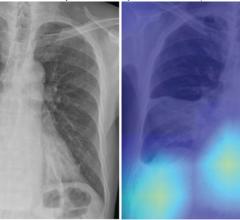

Lung Imaging

News and new technology innovations concerning how imaging technology for the lungs. This includes computed tomography (CT), X-ray and ultrasound imaging of the lungs to diagnose and monitor treatment for lung cancer, COPD, pulmonary embolism (PE), pneumonia, tuberculosis and COVID-19 can be found on this channel.